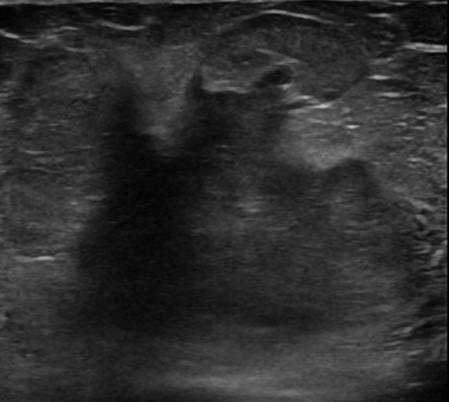

Ung thư vú

» Thông tin: Nữ giới – 76 tuổi.

» Lâm sàng: Khối tuyến vú.